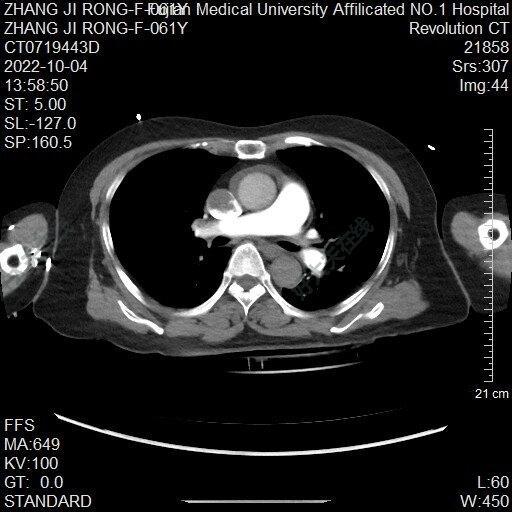

治療前 患者突發(fā)昏厥1次伴胸痛1小時(shí) 突發(fā)意識(shí)不清,心肺復(fù)蘇后送至急診 治療中 考慮患者急性肺動(dòng)脈栓塞引起呼吸心跳驟停,心肺復(fù)蘇成功后,出現(xiàn)瞳孔散大,給予治療量抗凝,強(qiáng)心,呼吸支持等,考慮患者心率血壓較前平穩(wěn),瞳孔對(duì)光反射恢復(fù),仍在呼吸機(jī)輔助呼吸,與患者溝通后,愿意積極搶救,準(zhǔn)備行“下腔靜脈濾器植入?肺動(dòng)脈造影?抽栓”,手術(shù)順利,順利抽出血栓 治療后 治療后1月 患者一般情況良好,返院取出濾器,無(wú)胸悶氣促等不適,復(fù)查CTA無(wú)明顯血栓征象